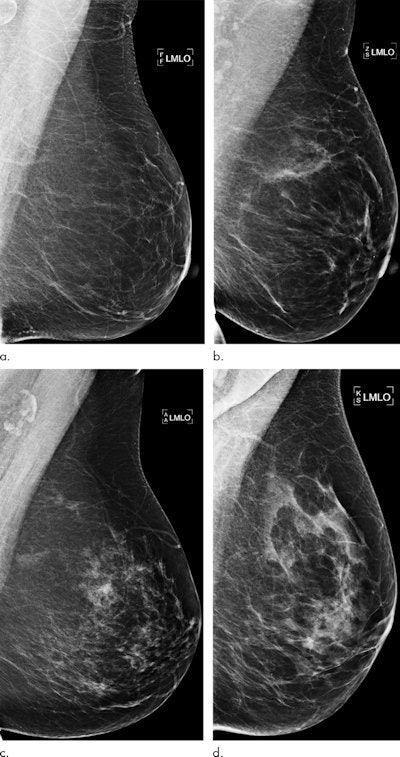

An artificial intelligence (AI) algorithm that analyzes negative screening mammography exams yielded better predictions for a woman's future risk of breast cancer than risk models based on breast density measurements in a recent study, published online December 17 in Radiology.

After performing retrospective testing on over 2,000 women, a group of researchers from Sweden found that risk scores provided by their deep-learning model correlated better than breast density-derived risk scores with the subject's diagnosis of cancer within a year.

High breast density is considered a risk factor for cancer, but current prediction models may not fully exploit all the rich information found in mammography images, according to the researchers. This additional information could potentially identify those women who would benefit from additional screening with MRI.